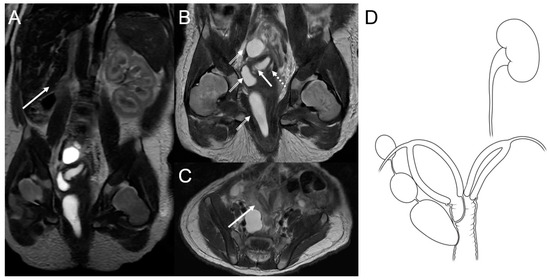

A magnetic resonance imaging (MRI) scan of the baby’s abdomen and pelvis was done to see how three cystic masses were related to the vaginal wall. The MRI, performed on the fourth day after birth, revealed agenesis of the right kidney with a compensatory hypertrophied left kidney (Figure 3A), uterine didelphys, an obstructed right hemivagina with hydrocolpometra, a non-obstructed left hemivagina, and three cystic lesions along the right hemivagina. These cystic lesions were thought to be tubulocystic anomalies (Figure 3B,C). Therefore, the diagnosis of OHVIRA syndrome and Gartner duct cyst was established (Figure 3D).

Figure 3.

(A) Coronal T2-weighted abdominopelvic magnetic resonance image showing an absent right kidney (arrow) with compensatory left kidney hypertrophy. (B) Coronal T2-weighted image of the pelvic area showing uterine didelphys with an obstructed right hemivagina and hydrocolpometra (arrow) as well as the non-obstructed left hemivagina (dotted arrow). Three cystic lesions along the right hemivagina were thought to be tubulocystic anomalies, suggesting a diagnosis of Gartner duct cysts (double-lined arrows). (C) Axial T2-weighted images showing uterine didelphys (arrow). (D) Schematic diagram of OHVIRA syndrome and possible Gartner cysts.